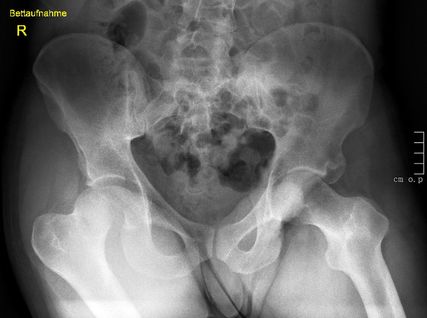

Abb. 1: Neben der klinischen Erstuntersuchung und Anamnese umfasst die Diagnostik die konventionelle native Röntgendiagnostik des verletzten Hüftgelenkes mit Standardaufnahmen im a.-p. und axialen Strahlengang. Abgebildet wird die erste Röntgenaufnahme (Hüftübersicht) nach Einlieferung in den unfallchirurgischen Schockraum nach Verkehrsunfall

Neben der klinischen Erstuntersuchung und Anamnese umfasst die Diagnostik die konventionelle native Röntgendiagnostik des verletzten Hüftgelenkes mit Standardaufnahmen im a.-p. und axialen Strahlengang (Abb. 1, 2) sowie gegebenenfalls die Anfertigung von Ala- und Obturatoraufnahmen. Obligatorisch empfehlen wir die Anfertigung eines Hüftübersichtsröntgens und gegebenenfalls, sofern möglich, auch eine Faux-Profil-Aufnahme. Zur präoperativen Planung und zur Beurteilung des Repositionsergebnisses ist der Goldstandard die Computertomografie (Abb. 3) mit Anfertigung einer 3D-Rekonstruktion. Im Rahmen der Notfalldiagnostik spielt die Magnetresonanz keine wesentliche Rolle. Im Hinblick auf die Diagnostik sekundär auftretender Komplikationen ist jedoch die Bedeutung des MRT unumstritten.

Klinisch zeigen sich typischerweise eine Innenrotation, Adduktion und Verkürzung des betroffenen Beins. Von Hüftkopffrakturen betroffen sind fast ausschließlich Männer im Alter von 18–30 Jahren und meist kommt es zur Luxation nach dorsal (ca. 75%), sehr selten auch nach ventral (ca. 25%).